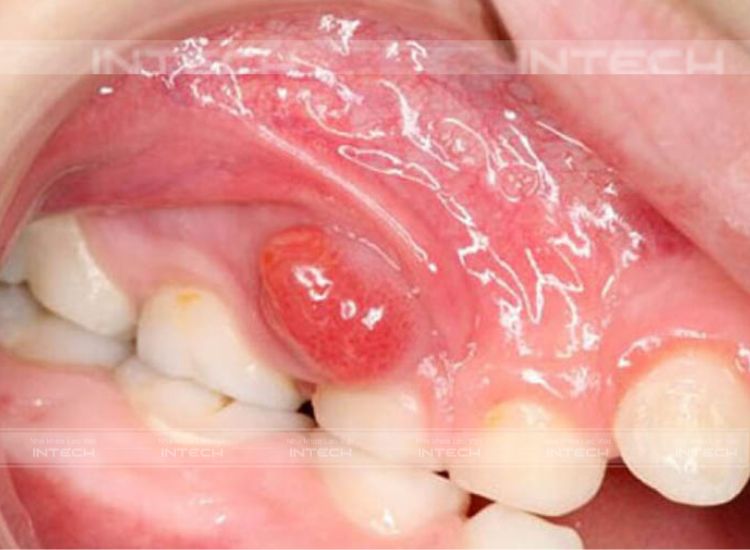

Áp xe nướu

Đây là áp xe nướu, nằm ở giữa răng và nướu. Vi khuẩn sẽ sinh sôi và phát triển trong trường hợp người bệnh không vệ sinh răng miệng đúng cách. Lúc này, vi khuẩn sẽ phá hủy các mô, tạo thành các ổ áp xe và tiếp tục phát triển.